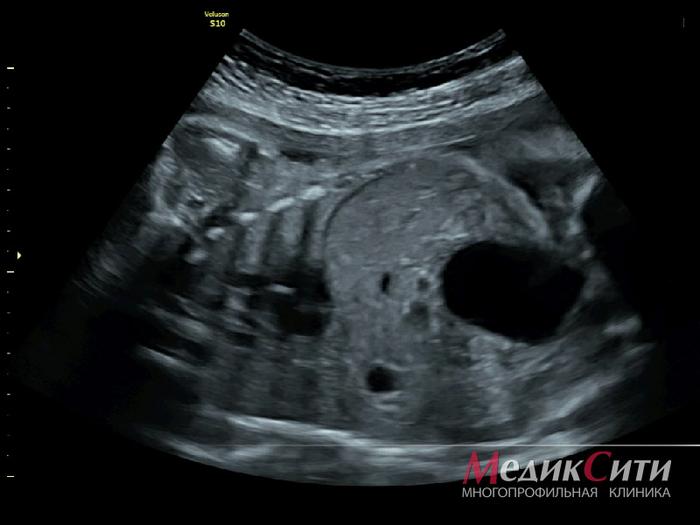

Снимок ультразвукового исследования (УЗИ) при беременности выглядит как черно-белое изображение, на котором можно увидеть контуры плода, его органы и околоплодные воды. На изображении могут быть различимы такие структуры, как головка, конечности, сердце и различные органы малыша, а также плацента и матка.

Четкость и качество снимка зависят от сроков беременности, оборудования и уровня подготовки специалиста. На ранних сроках изображение будет менее детализированным, но к третьему триместру можно отчетливо увидеть крупные анатомические особенности плода, что помогает врачам оценить его развитие и здоровье.

Обычное ультразвуковое исследование представляет собой последовательность двухмерных плоских снимков плода или его органов.